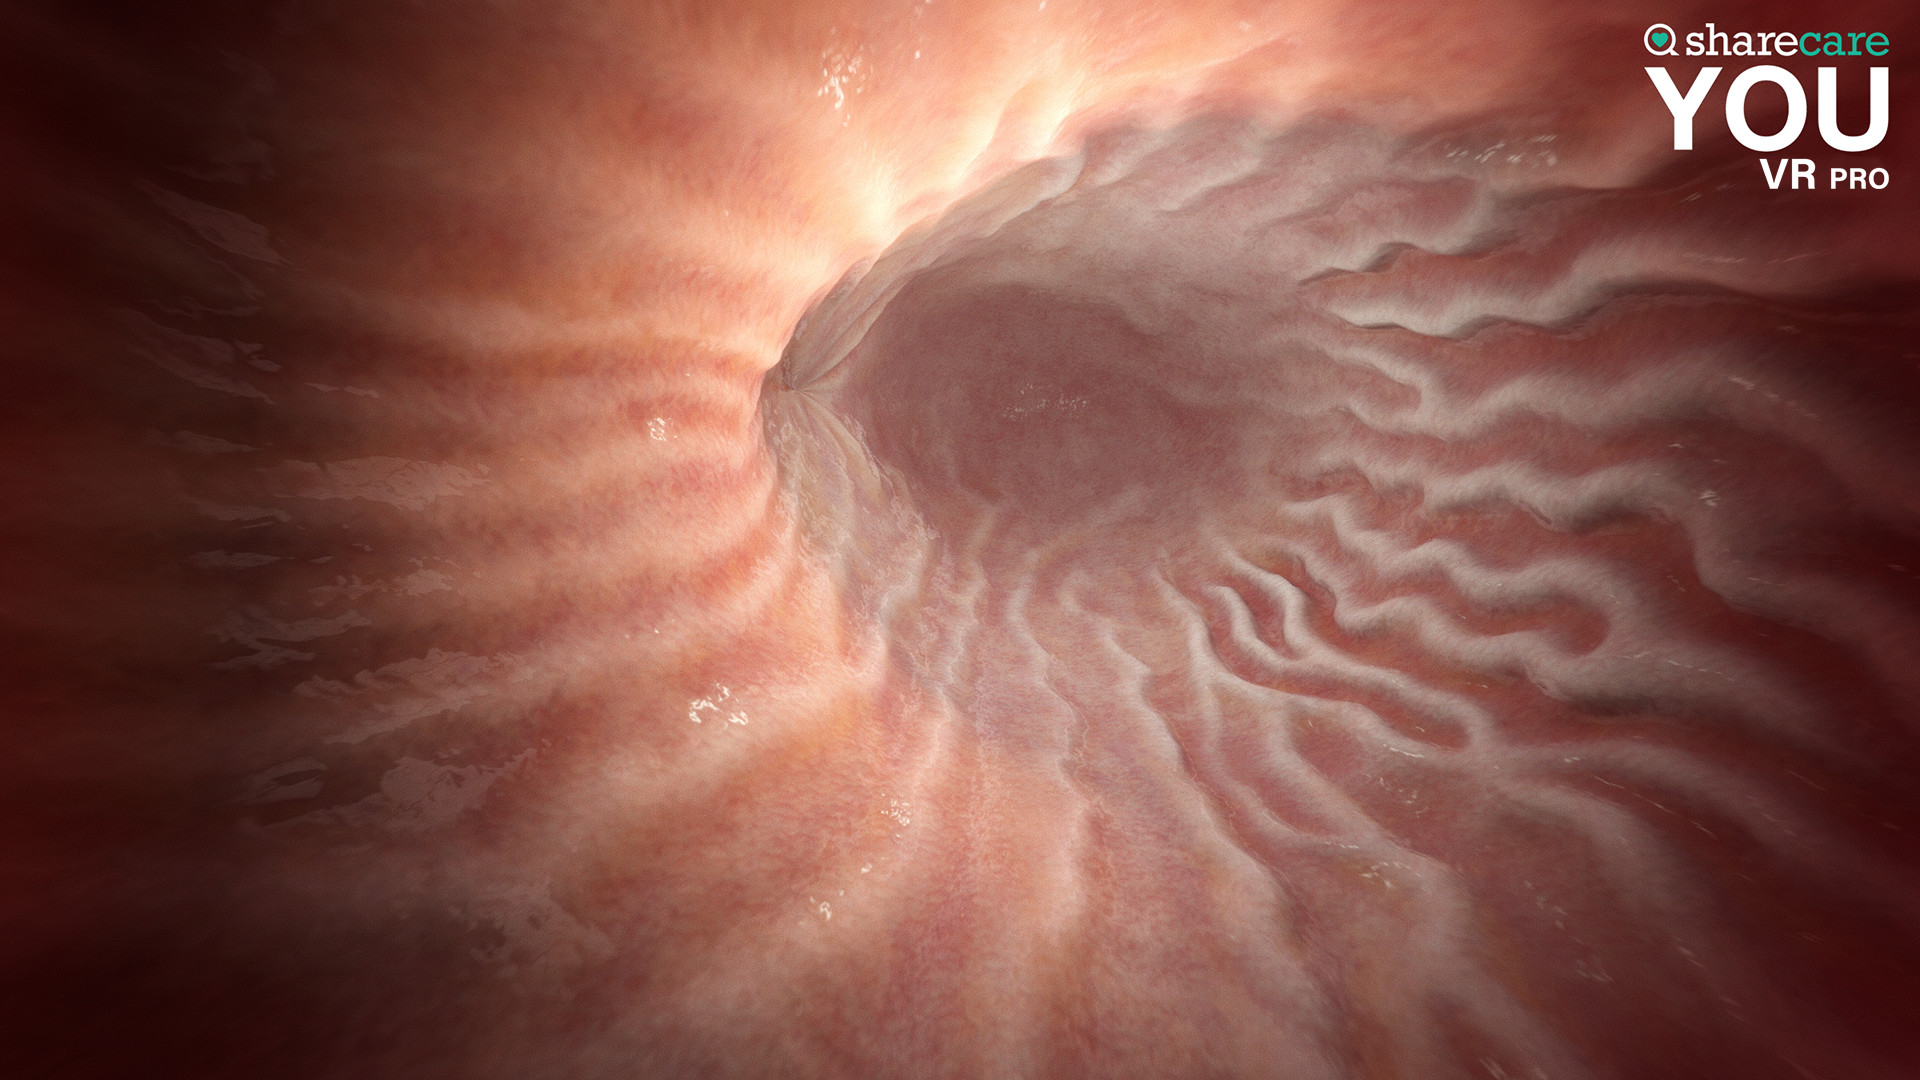

The winner of the 2019 Appy Best VR App is now available on Mac and PC, with more content, bolder graphics, and enhanced features! Sharecare YOU VR is a fully immersive, photorealistic simulation of the human body, enabling anyone to explore its astonishing details in full 360 degrees. Interested in learning about a specific organ? With the click of a button, travel inside, visualize its natural function, and dive deeper. Want to learn even more? Check out the many tags and labels along the way to gain even more information and insight. Easily customize YOU to better understand physiology and simulate disease. You can even personalize our avatars to be a virtual you – your health, your conditions. It really is all about YOU. With YOU VR PRO, users can create visually compelling, high-quality educational content. Build YOU lectures and presentations easily, with the help of video and voiceover recording, and the ability to draw and add your own text. You can also be the star within these videos using our web-cam feature.

- YOU content - an expanding library of over 40 different scenes to explore including anatomy, physiology, conditions, and treatments